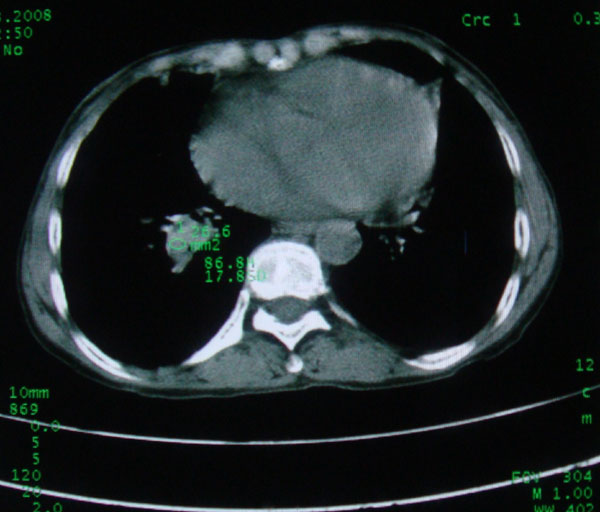

标题: CT15046:F59Y,咳嗽间断咳血丝痰就诊. [打印本页]

咳嗽\间断咳血丝痰就诊.

本例应该是“慢性疾病并发多种合并症”即:慢支并感染并支气管扩张征!结合病灶分布 形态分析,不除外合并“继发性肺结核”!

肺间质性改变 支气管扩张合并感染

慢性支气管炎伴全小型肺气肿、支气管扩张、感染、间质纤维化。

慢性支气管炎伴支气管扩张、感染,间质纤维化。

慢性支气管炎伴全小叶型肺气肿、支气管扩张、感染、间质纤维化